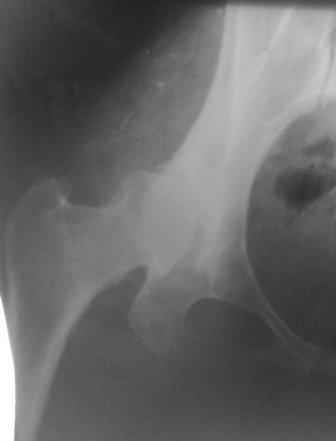

Типичная концовка проигнорированного диспластического состояния сустава. Дисплазия тазобедренного сустава часто встречающаяся патология у жителей Центральной Азии вследствие тугого пеленания в детстве. Традиционно ребенок находится в течение дня в так называемой кроватке "бешик", удобной в быту, но она впоследствии приводит к недоразвитию тазобедренного сустава.

У женщин болезнь клинически проявляется после беременности болями в суставе. Но во время беременности из-за невозможности рентген обследования проблема игнорируется, и упускается время. После беременности симптомы исчезают, и проявляются во время следующей беременности или после увеличения веса.

Данный сустав в начальной стадии разрушения, но все-таки я бы сделал обзорный таз и отдельные снимки сустава в 30 градусной абдукции и аддукции. Также снимки с внутренней и наружной ротацией для оценки состояния головки бедра.